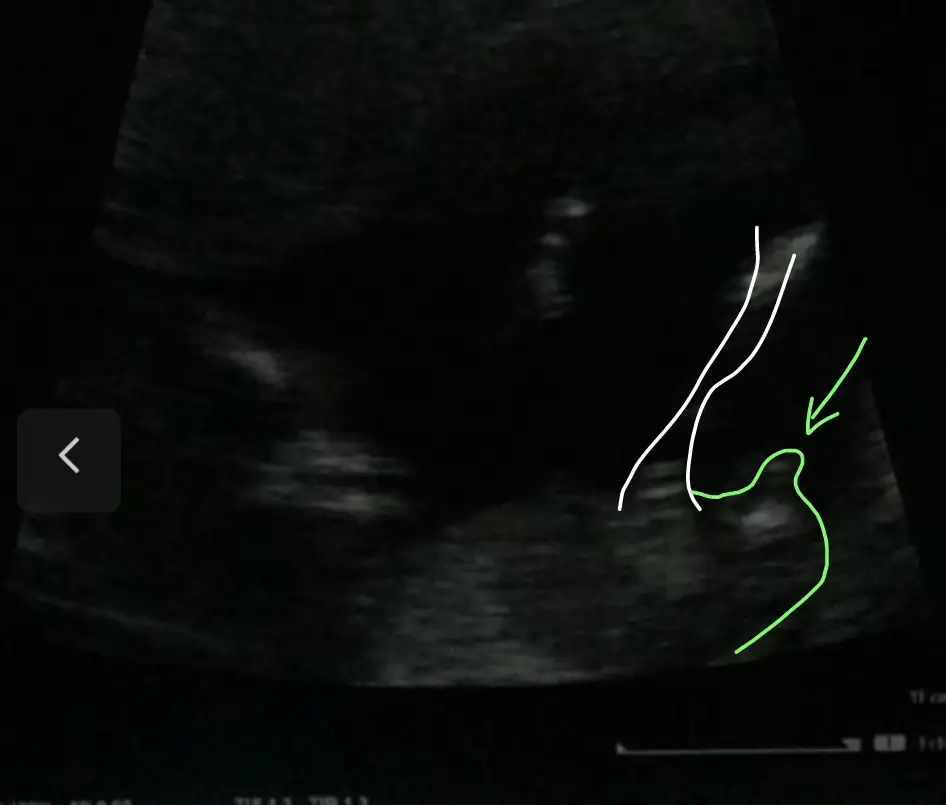

USG göre kız gibiydi 🤗 sağlıkla gelsin oğlusun 💙 bakın benim suçum yok çizdim 🙈Eki Görüntüle 2819617

Çok teşekkürler. Ramiz teorisine göre de kız demişti arkadaş vlla ne yalan söyleyeyim bende kız istiyordum bi oğlum vardı. Nasip gördük bugün pipiyi 16. Haftadayız değişmez herhalde 😅